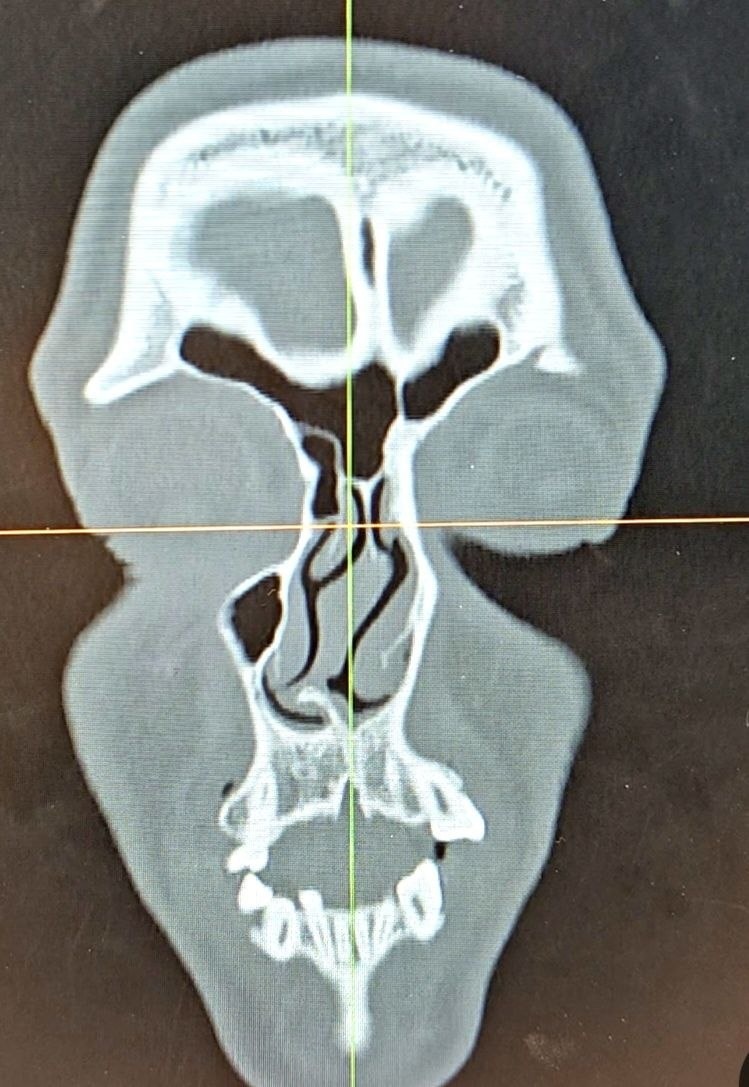

Результат на столе - функциональная риносептопластика кривого носа с грубой деформацией перегородки

Результат на столе - функциональная риносептопластика кривого носа с грубой деформацией перегородки.